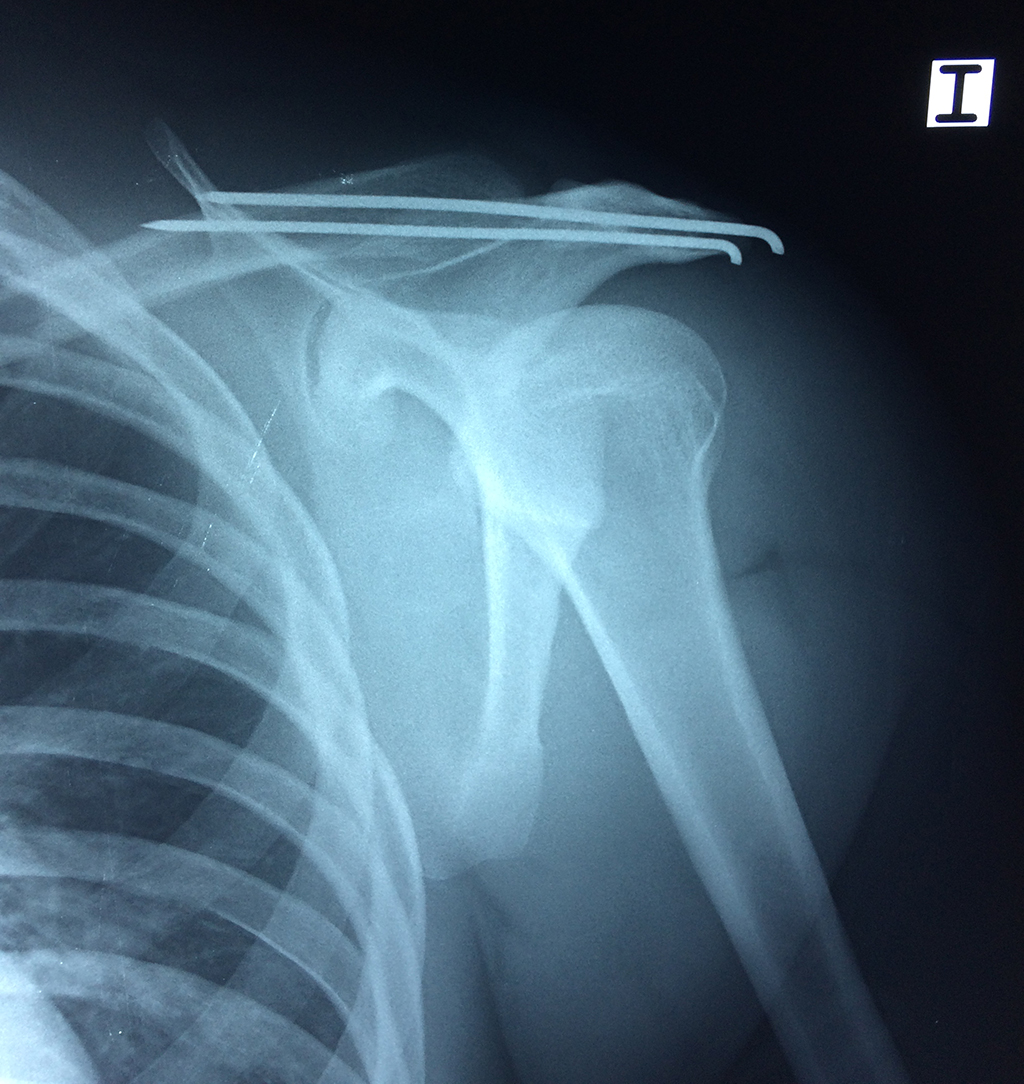

Exteriormente una envoltura de tejido blando circunda el conjunto, es la llamada cápsula articular que está reforzada por varios ligamentos que le dan estabilidad e impiden que los huesos se desplacen más allá de sus límites fisiológicos. Un conjunto de músculos y sus tendones se unen a las superficies de los huesos y hacen posible la movilidad de la articulación, entre ellos es muy importante el manguito rotador formado por cuatro músculos que proporcionan movilidad y estabilidad al hombro.

Varias estructuras transparentes en forma de saco llamadas bolsas serosas, permiten el deslizamiento suave de los diferentes componentes móviles. El hombro es la articulación con mayor amplitud de movimientos del cuerpo humano.